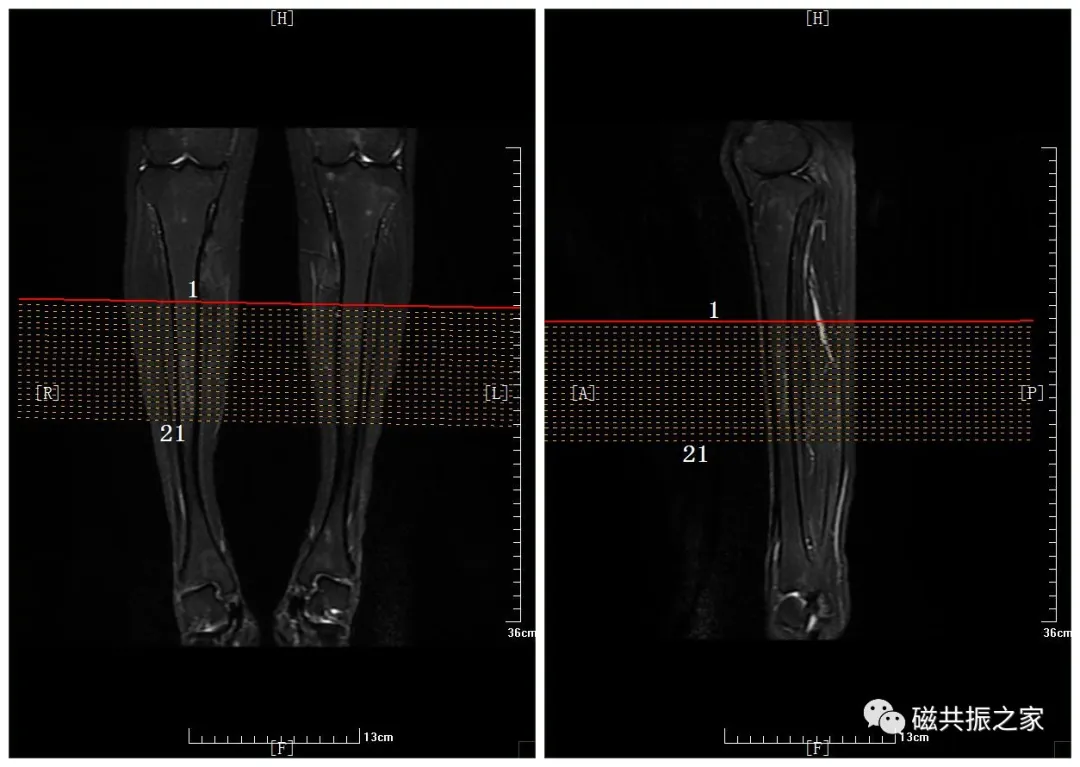

冠状面:COR T1 FSE 冠状位T1加权序列

在横断位和矢状位上定位。在横轴位上调整定位线,双侧对称扫描;在矢状位上调整定位线使其平行于长骨长轴。两端尽量包全两端关节,如不能包含两侧,至少需包含临近患侧关节;需包括整个病变。

冠状位:COR STIR 冠状T2加权脂肪抑制序列

复制COR T1 FSE,采用DiXON序列也可。

长骨的扫描常采用“长轴+短轴”相结合的体位扫描,优先选择自旋回波序列扫描。矢状、冠状及横轴面均需扫描T2WI的脂肪抑制序列,选择两个显示病变较好的体位行T1WI序列扫描。如需增强扫描可分别行AX、COR、SAG的增强扫描,造影剂:0.2mml/kg或者0.1mmol/kg。